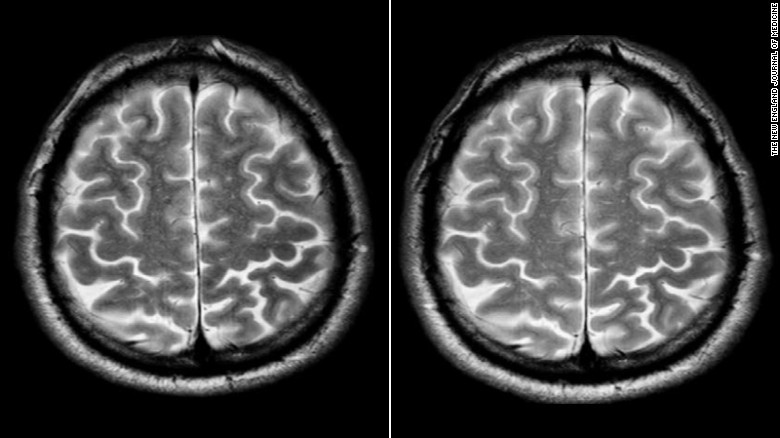

Não bộ của phi hành gia trước và sau khi tham gia vào chuyến du hành ngắn hạn

Việc tích dịch (bao gồm máu và dịch não tủy) từ các cơ quan khác lên sọ não do thay đổi trọng lực sẽ khiến gương mặt của chúng ta căng phồng, trong khi tứ chi thì teo nhỏ lại.

Theo các chuyên gia, nitric oxit có trong cơ thể sẽ khiến các mạch máu giãn nở ra quá mức. Điều này kéo theo việc tăng lượng máu đến não, gây nên áp lực quá mức lên hàng rào máu-não. Kết quả là hiện tượng phù (oedema) xảy ra trên não bộ.

Đây cũng là "thủ phạm" gây nên các triệu chứng mờ mắt, đau đầu và buồn nôn khi áp lực sọ não tăng lên do ứ một lượng dịch đáng kể.

Mặt khác, trong một cuộc khảo sát về thị lực ở 27 phi hành gia của NASA - những người có thời gian ở trên trạm không gian ISS trung bình là 108 ngày - thì đa số đều gặp các vấn đề về mắt.

Kết quả MRI (chụp cộng hưởng từ) cho thấy, 9 phi hành gia có dấu hiệu phồng dây thần kinh thị giác ở sọ não.

Ngoài ra có 6 người nữa có nhãn cầu bị dẹt ở phía sau, ảnh hưởng phần nào đến thị giác mà nguyên nhân vẫn chưa có lời giải đáp.